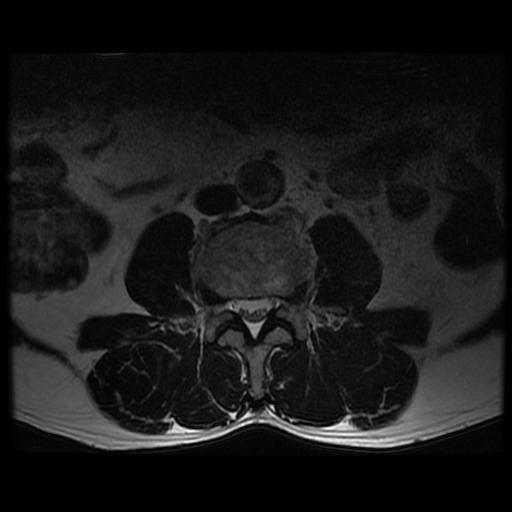

| Study | ID | Date | Accession # | Thumbnails | Report | XR ELBOW, AP & LAT, LEFT | 2766356 | 08/21/2019 | 2766356 | ... | MR WHOLE SPINE (FULL STUDY) | 32376 | 08/23/2019 | 2766095 | ... | XR CERVICAL SPINE, AP & LATERAL | 2765876 | 08/20/2019 | 2765876 |